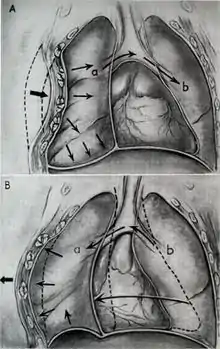

The characteristic paradoxical motion of the flail segment occurs due to pressure changes associated with respiration that the rib cage normally resists:

- During normal inspiration, the diaphragm contracts and intercostal muscles pull the rib cage out. Pressure in the thorax decreases below atmospheric pressure, and air rushes in through the trachea. The flail segment will be pulled in with the decrease in pressure while the rest of the rib cage expands.

- During normal expiration, the diaphragm and intercostal muscles relax increasing internal pressure, allowing the abdominal organs to push air upwards and out of the thorax. However, a flail segment will also be pushed out while the rest of the rib cage contracts.

Paradoxical motion is a late sign of flail segment; therefore, an absence of paradoxical motion does not mean the patient does not have a flail segment.